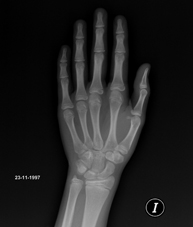

Procedimiento mediante el cual, utilizando rayos X, se obtienen imágenes de la pelvis para su estudio, especialmente de los huesos pélvicos. - RX Edad ósea

Estudio que mediante una radiografía de la mano permite valorar, en función del desarrollo de los huesos, la edad del paciente y determinar si existe un retraso o un crecimiento superior a lo que corresponde para su edad. - RX Caderas pediatría

Técnica mediante la cual, utilizando rayos X, se obtienen imágenes del cavum para su estudio. Indicaciones: dificultad respiratoria, regurgitación, otitis de repetición. - RX Edad ósea

Estudio que mediante una radiografía de la mano permite valorar, en función del desarrollo de los huesos, la edad del paciente y determinar si existe un retraso o un crecimiento superior a lo que corresponde para su edad. - RX Senos paranasales